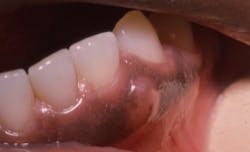

The patient is 49-year-old Lewis who has entered your practice today for a routine visit. He is being treated for hypertension, consumes alcohol in moderation, and is a nonsmoker as of his last appointment. When you ask him if he has noticed any changes in his body, including his mouth, he points to the enlarged area in the lower left quadrant (see Figure 1). He has noticed this “bump” and is especially aware of it when he flosses.

Perioral and intraoral characteristics: The gingival cyst appears as a nodule that is painless, smooth, nonblanching, and may be normal in color. The area is usually nonmobile, flesh-colored with a light blue hue in some cases, and a firm nodule that may be slightly depressed with pressure.

Distinguishing characteristics: The tooth will test vital unless prior damage has occurred to the pulp from other sources. The GCA will usually not appear radiographically distinct unless the cyst is large and emits pressure on the bone, creating resorption leading to a depression (see Figure 2).